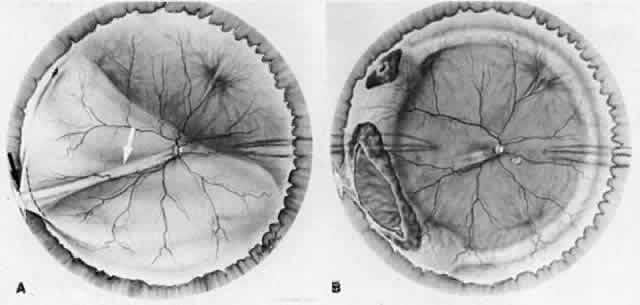

fibrocellular proliferation.15–17 Intermediate Secondary Complications of Ocular Penetration Cleary and Ryan15 reported experimental evidence that blood and, to a lesser extent, lens

material in the presence of a large scleral wound caused fibrocellular

proliferation and membranes, the contraction of which produced tractional

retinal detachments (Fig. 4). The clinical consequences of fibrocellular proliferation and membrane

contraction are well established and include traction retinal detachments, retinal

breaks, rhegmatogenous retinal detachments, proliferative

vitreoretinopathy, cyclitic membranes, ciliary body detachments, hypotony, and

phthisis bulbi.  Fig. 4. Fibrocellular proliferation and membrane formation cause tractional retinal

detachment. (Cleary PE, Ryan SJ: Method of production and natural history of experimental

posterior penetrating eye injury in the rhesus monkey. Am J Ophthalmol 88:219, 1979. Published with permission from The American Journal

of Ophthalmology. Copyright by The Ophthalmic Publishing Company.) Fig. 4. Fibrocellular proliferation and membrane formation cause tractional retinal

detachment. (Cleary PE, Ryan SJ: Method of production and natural history of experimental

posterior penetrating eye injury in the rhesus monkey. Am J Ophthalmol 88:219, 1979. Published with permission from The American Journal

of Ophthalmology. Copyright by The Ophthalmic Publishing Company.)